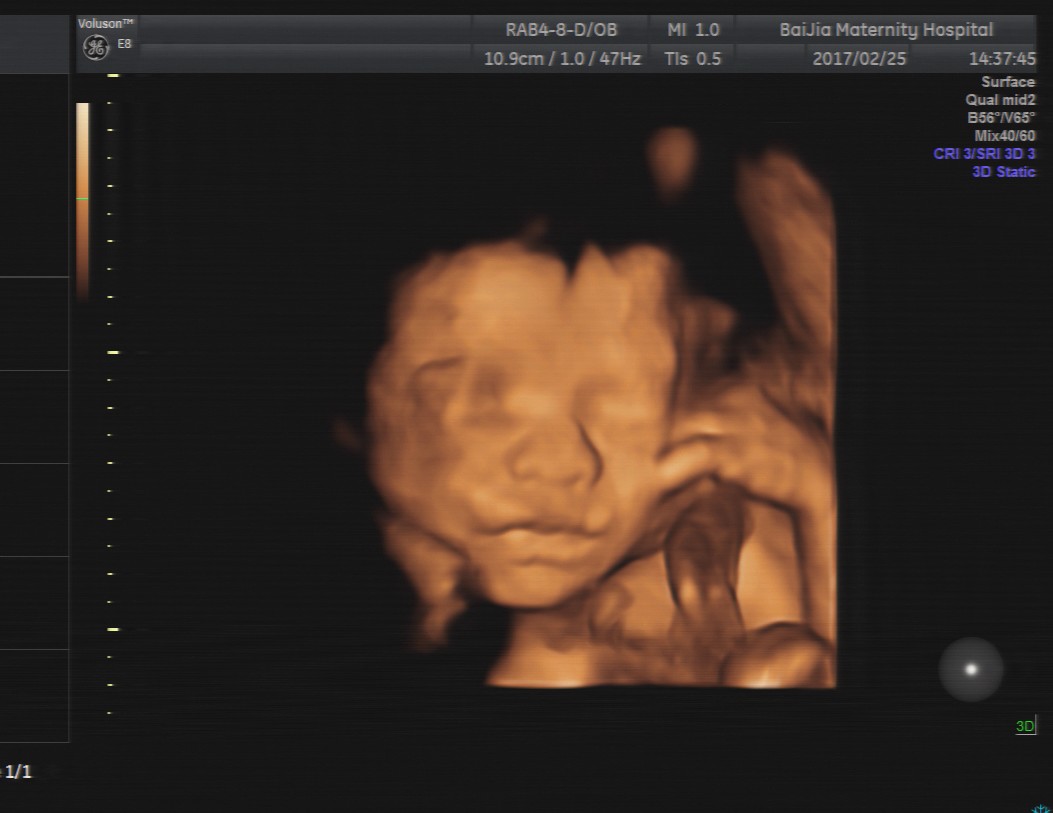

第一种:四维彩超是利用超声仪器中的软件将二维的平面图像模拟转换成动态、立体四维图像,有利于医生判断宝宝的发育情况是否正常以及是否存在重大畸形。检查时胎宝胎动比较频繁、表情动作也较多,像打哈欠、吸吮手指、吞咽口水等等,这些画面通过超声仪器呈现出来可能并不是那么好看。

第二种:胎宝宝的成长需要依附胎盘,所以面部可能紧贴着胎盘或者子宫壁引起变形,因此,在四维彩超成像时,宝宝的面部往往模糊不清,或某一部分直接变形,感觉比较丑。

第三种:四维彩超最佳检查时间段是孕20—24周,这个时期胎宝宝的各个器官刚刚发育完全,面部并不丰满,而四维彩超的成像是个放大的过程,所以可能出现大嘴、大鼻子、大脑门的外貌,看起来丑丑的。